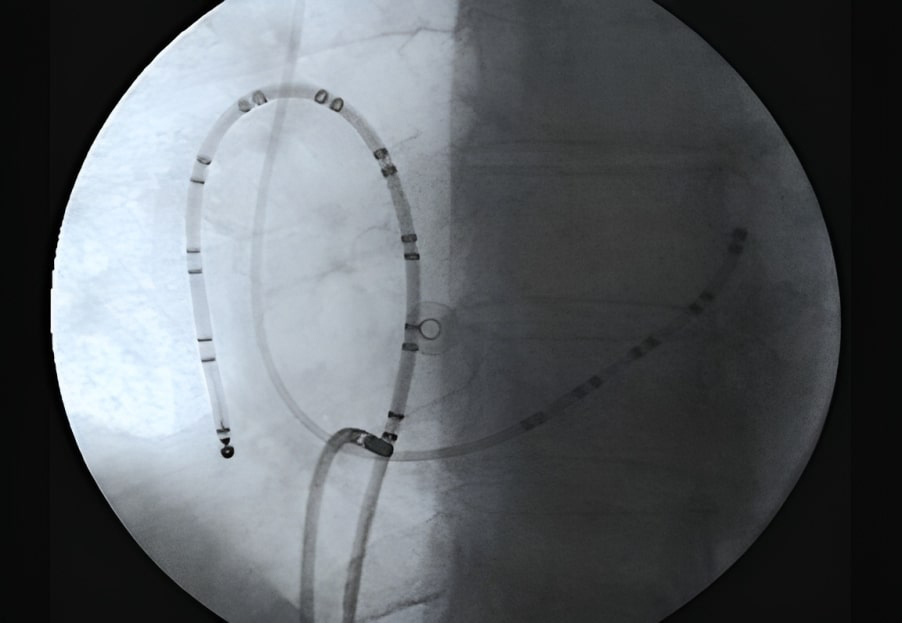

Ablation can be performed in sinus rhythm or during flutter (Fig. 6). If electrocardiogram (ECG) is typical and the patient has no history of cardiac surgery or previous ablations, CTI ablation can be performed directly in sinus rhythm without induction. However, in patients with previous cardiac surgery or non-completely typical ECG, it is necessary to confirm the involvement of the right atrium and the CTI in the circuit using pacing mapping techniques during spontaneous or induced atrial flutter [95, 96, 97].

Fig. 6.Electrocardiographic and electrophysiological tracings in typical atrial flutter. Left panel: Surface ECG of counterclockwise flutter with 2:1 ventricular conduction. Right panel: Endocavitary tracings of a counterclockwise flutter showing in the recordings from duodecapoles catheters relatively fast caudocranial activation of septum (pairs A10 to A7) followed by superior part of RA (A6-A5), lateral wall (A4-A1) and finally CTI (ABLd). LA is activated proximal to distally, secondarily from this circuit (coronary sinus tracings CSp to CSd). ECG, elcetrocardiogram; CTI, cavotricuspid isthmus; LA, left atrium; RA, right atirum; CSp, proximal coronary sinus; CSd, distal coronary sinus.